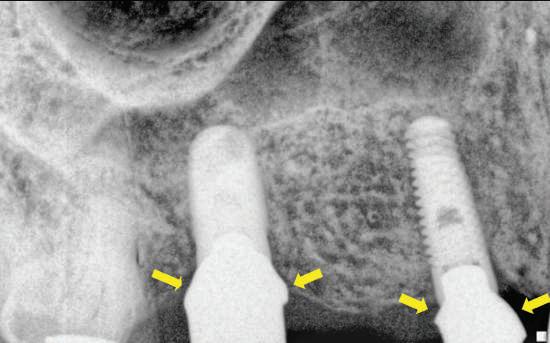

EXTINDEREA PROTOCOALELOR DE TRATAMENT

Protocoalele de tratament au fost dezvoltate într-un mod ce a facilitat confortul şi controversa. De exemplu, în trecut, protocolul standard prevedea permiterea integrării implantului, cu menţinerea sa neîncărcată pentru 6 luni la maxilar şi 3 luni la mandibulă ca timp minim de vindecare. În prezent industria asistă la protocoale care permit încărcarea la 3 săptămâni şi, desigur imediat în momentul inserării implantului.

Ceea ce odată reprezenta protocol "universal" s-a transformat acum într-un număr de protocoale ce depind de forma implantului, suprafaţa şi validarea prin studii pro- şi retrospective. Clinicianul trebuie să procedeze cu

precauţie când încearcă să traducă informaţiile dintr-un sistem/protocol de implantare în altul, pentru că ele nu se pot transpune într-un mod universal. Conceptul de "universal" ţine de trecut. Astfel, în loc să fie inserate "acolo unde este os", implanturile se plasează într-o abordare ghidată de principiile restauratoare.

Protocoalele de încărcare au fost scurtate, în mare parte datorită tratamentelor de suprafaţă îmbunătăţite. Microsuprafeţele care promovează integrarea rapidă sunt responsabile pentru duratele mai scurte de integrare. Geometria implanturilor a favorizat stabilitatea sporită la inserţie pentru protocoalele cu încărcare imediată.